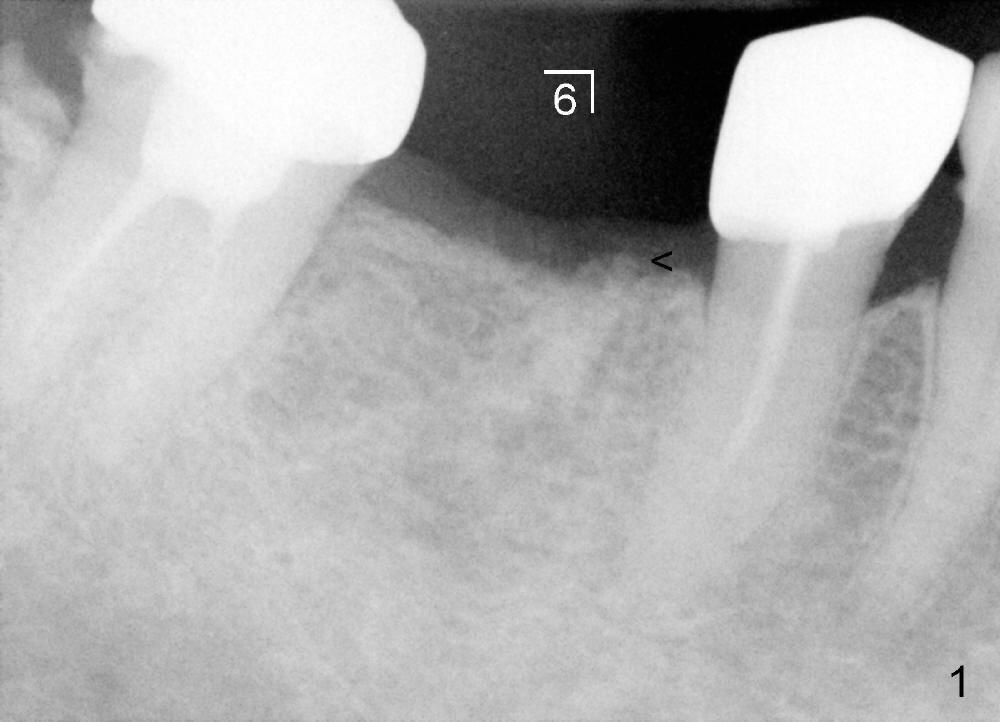

六十三岁台湾太太两年前右下第一磨牙准备做植牙,术前X光片显示缺牙区近中牙槽脊骨质好像有些特殊(图一箭头)。六乘十七毫米植牙(I)刚植入(图二,做了bone expansion),近中骨质好像又没有问题(箭头)。六个月后植牙近中骨质游离(图三箭头),除去骨片后,牙龈愈合,一个月后戴上牙冠(图四C),近中骨质仿佛没有异常。一年半后,病人突然回诊所,抱怨植牙周围流出臭味水,有些压痛。检查发现牙冠近中有个瘘道(图六箭头),下面好像有游离骨片,植牙牢靠,根尖片显示近中上部骨质稀疏(图五*),游离骨片(箭头)。翻开牙龈,除去相当大游离骨片,植牙粗糙面暴露(图七*,原有游离骨片所在地),除去炎性肉芽组织(+ +)后,植牙上部一两个螺纹暴露,箭头表示骨缺损边缘。反复用生理盐水冲洗,然后稀释四环素溶液冲洗,用探针和curet轻轻刮除植牙表面和螺纹菌斑,涂Straumann PrefGel,又用生理盐水冲洗,涂Endogain,植入Rocky Mountain Irradiated Allogenic Cancellous Bone and Marrow (图八*)。沐旭生医生认为植骨可能不管用,细菌很难清除,最好拔除植牙,植骨,然后再植牙。病人自己也意识到这个可能性,现在只有希望奇迹出现:缺损太大,不植骨身体可能无法修复。